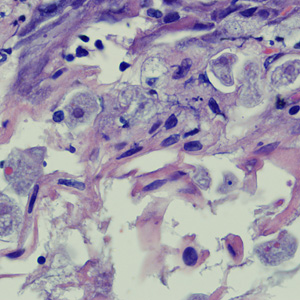

A biopsy was performed on a 23-year-old woman with no known travel history, presenting with a perianal ulcer. The specimen was preserved in formalin and sent to a pathology lab for work-up. Figures A and B show what was observed at 500x magnification from a section of the tissue, stained with hematoxylin and eosin (H&E). What is your diagnosis? Based on what criteria?

Figure A